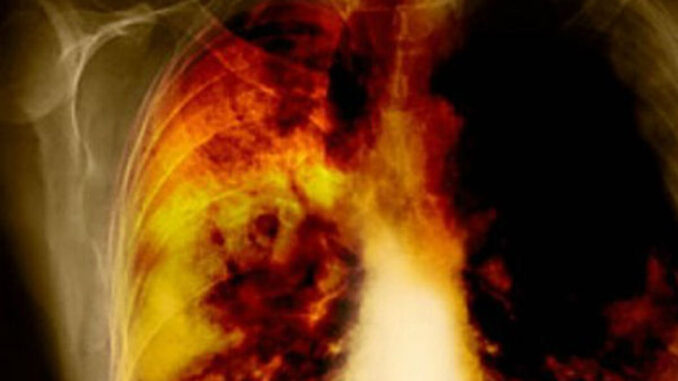

Ovaj napitak bi trebali piti i pušači i nepušači kako bi izbacili toksine iz pluća.Za pripremu napitka koji čisti pluća, potrebno vam je:400 grama luka,1 litra vode,400 grama šećera (želite li zdraviju varijantu koristite med ili javorov sirup),2 kašike kurkuma,korijen đumbira veličine palca.

Uzmite dvije kašičice eliksira ujutro na tašte te navečer dva sata poslije obroka.Uporan kašalj karakterističan je simptom bakterijskih ili virusnih infekcija disajnih organa, koje prati i gusti sekret u grlu, sinusima i plućima, koji je zalijepljen za zidove naših bronhija pa se vrlo teško izbacuje